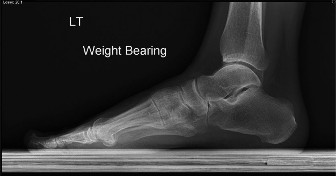

A 31-year-old female presents to your office with increasing pain over the posterior medial ankle and stiffne…